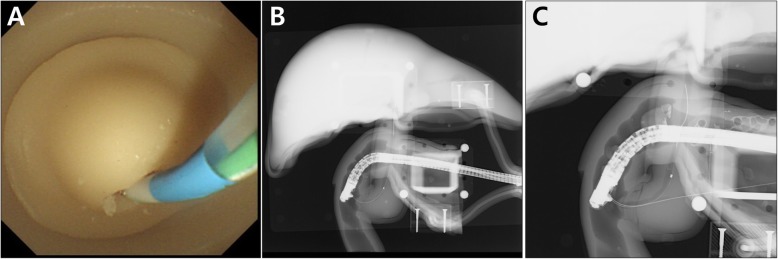

Using the basic module, biliary cannulation was easily and repeatedly achieved with a guidewire (VisiGlide 2™, Olympus Co., Tokyo, Japan; or gSlider, Medwork GmbH, Aisch, Germany) and cannulation catheter (ERCP-catheter, MTW-Endoskopie, Wesel, Germany) (Fig. 5a and b). Biliary cannulation with double guidewire method and difficult cannulation were also successfully achieved using the CBD stricture modules (Fig. 5c). Despite repeated procedures, the ampulla portions of each module did not suffer damage or tears. Also, we did not need to repeat injecting the dye into the CBD modules due to excellent visualization of biliary tract under the fluoroscope.

Biliary stent placement was implemented using the distal stricture and proximal dilation CBD module (Fig. 6). After the insertion of self-expandable metal stent (SEMS) (Hanarostent®, M.I.Tech, Pyeongtaek, Korea) through the stricture area, the SEMS was retrieved again, and was reinserted into the deploying catheter for repeated procedures. Plastic stent insertion and endoscopic balloon dilation were also successfully performed using the same module.

In order to make the experience of being placed around the duodenal ampulla and the feeling of using various ERCP accessories as realistic as possible, 3D modeling data were obtained from human CT images, as per previous reported studies [ref. 13–ref. 15]. One of important steps in this process was to make the stomach and duodenum. We wanted to make a model where the duodenoscope could be inserted in a sequence that followed from esophagus, stomach, and duodenum, but since silicone material was not elastic and stretchable like the human stomach, we decided to cut the stomach for easy insertion of duodenoscope around the duodenal ampulla and omitted the shortening step. Therefore, insertion of the duodenoscope was not difficult, but the direction of the fluoroscopic image had to be inevitably adjusted because of the difference in direction as compared to an actual human (Fig. 5). Another important step in the designing process was to make the ampulla and CBD in various shapes. If this part could be made into various shapes, it could be implemented for various training models and disease models. In order to resolve this issue, we implemented a new 3D printing method to make these parts in various forms, and to connect them to the main body in a module-type assembly format. Another important step was to implement the sphincterotomy model. For the new model to be appealing and used widely in future, it was necessary that it should be more convenient, cost-effective, and reusable than the previous models. As mentioned for other modules, it had to be easily assembled with the main body, electrically operated, easy to store, and relatively inexpensive. Because the present silicone-material phantom utilizes injection molding technique, it can secure many economic benefits in re-production. Since re-production requires only silicone materials and injection molding efforts, we can save the cost of designing for positive phantom model and negative molder model, and the cost of 3D printing of negative molder as well. Therefore, it is possible to reproduce the same phantom at a price of one-third. Because the present phantom has modular configuration, in addition, it can be implemented with minimal efforts of designing and 3D printing for additional variant designs. While looking for suitable material, the curved Vienna sausage met all the conditions for eligibility and could be used in variable sizes and shapes. Also, it is very similar to the practice in the human body, and creating the sphincterotomy model was a very positive and reaffirming experience.